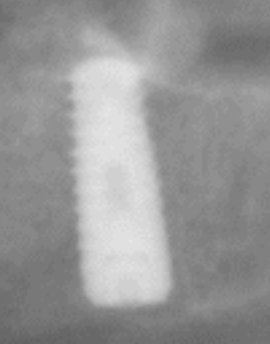

Buenas tardes, me podríais ayudar con la marca del implante? esta sacada de la orto , pero si no se ve claro puedo hacerle una periapical, muchas gracias de antemano

Buenas tardes, ¿me podria algun decir que tipo de conexion y marca de implante es? muchisismas gracias de antemano!

Por favor! Alguien sabe que marca de implante es? Gracias!